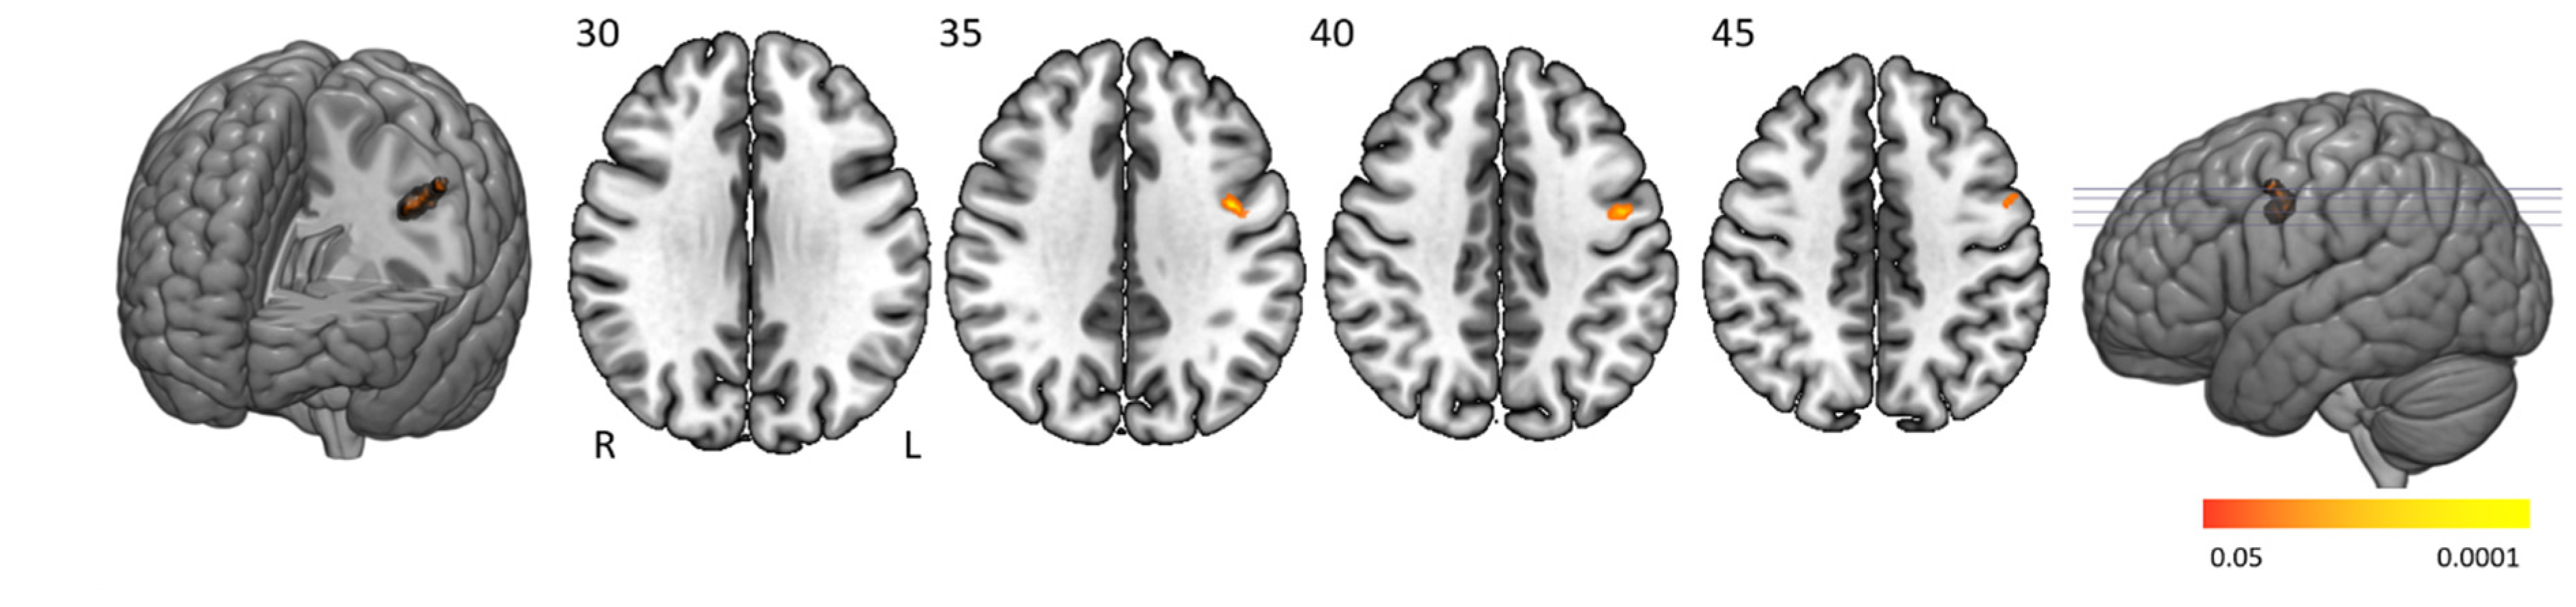

3.5. Error-Related Effect

People with narcolepsy type 1 had significantly lower activation than controls in the left pre- and postcentral cortex when making more errors (Figure 5 and Table 4). No significantly higher activation was found in people with narcolepsy type 1 compared to controls.

4.4. Error-Related Effects

People with narcolepsy type 1 had significantly lower activation than controls in the left pre- and postcentral gyrus when making more errors. The primary motor and primary somatosensory motor cortex are known to be involved in motor response inhibition [44,45] and activation in these regions seems reasonable as most errors were errors of commission where the button should not have been pressed. Previous studies have shown that people with narcolepsy in general experience difficulties in impulsivity and response inhibition, specifically under time pressure [46,47]. Our results could therefore reflect the motor preparation-related aspect of these cognitive problems.